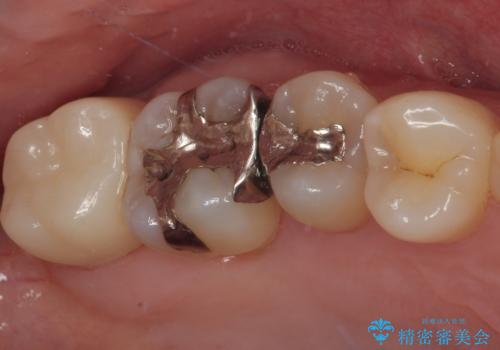

- 元々むし歯があったものの、処置が困難とのことでしたが、矯正治療を終えたので処置をしたいとのことで来院された患者様です。

左右ともに最後臼歯が頬側に顕著に突出しており、むし歯になってしまったことが想像されました。

矯正治療により処置が可能な位置に歯が移動したため、オールセラミッククラウンにて補綴治療を行うこととしました。

歯列が移動したとはいえ、左右ともに後方傾斜しており、むし歯の除去、形成(形を整える)、型取りの全てが非常に困難な処置となりました。